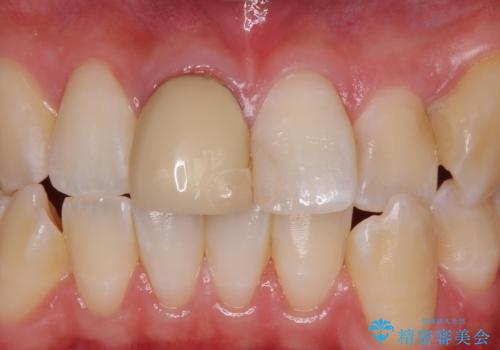

前歯の色が気になる。オールセラミッククラウンでのやり替え

- 前歯のかぶせ物の色が気になるとのことで来院された患者様です。

セラミッククラウンで作り変えていきます。

色・形ともに改善され、大変喜んでいただけました。